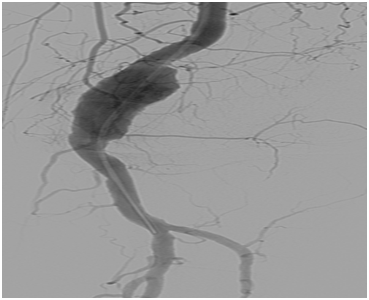

An otherwise fit 72-year-old man presented with left calf swelling. Initial investigations for DVT were negative but clinical examination revealed a Popliteal artery aneurysm. This was confirmed on duplex and subsequent CT angiography. The case was discussed at a multidisciplinary meeting and given the good landing zones in the proximal and distal popliteal artery the patient was put forward for endoluminal stenting. Given the slight tapering of the Popliteal artery a 8mmx5cm Viabahn stent was placed in the distal landing zone followed by a 9mmx10cm Viabahn, overlapped by 2cm and landed in the proximal popliteal. This was accomplished by a transfemoral antegrade approach. The stents were gently balloon impacted into the native artery and into the junctional region with a 9mmx4cm angioplasty balloon. Check angiography was satisfactory and stent expansion was confirmed with IVUS prior to the end of the procedure. The patient is alive and well 6 months post-stenting (Figure 3a-3d).

Figure 3a Intraprocedural digital subtraction angiogram pre- and post-stent deployment.

Figure 3b Post-stent completion angiography; note good coverage of lesion, no endoleak and preserved tibial vessels.

Figure 3c Post-stent completion angiography; note good coverage of lesion, no endoleak and preserved tibial vessels.